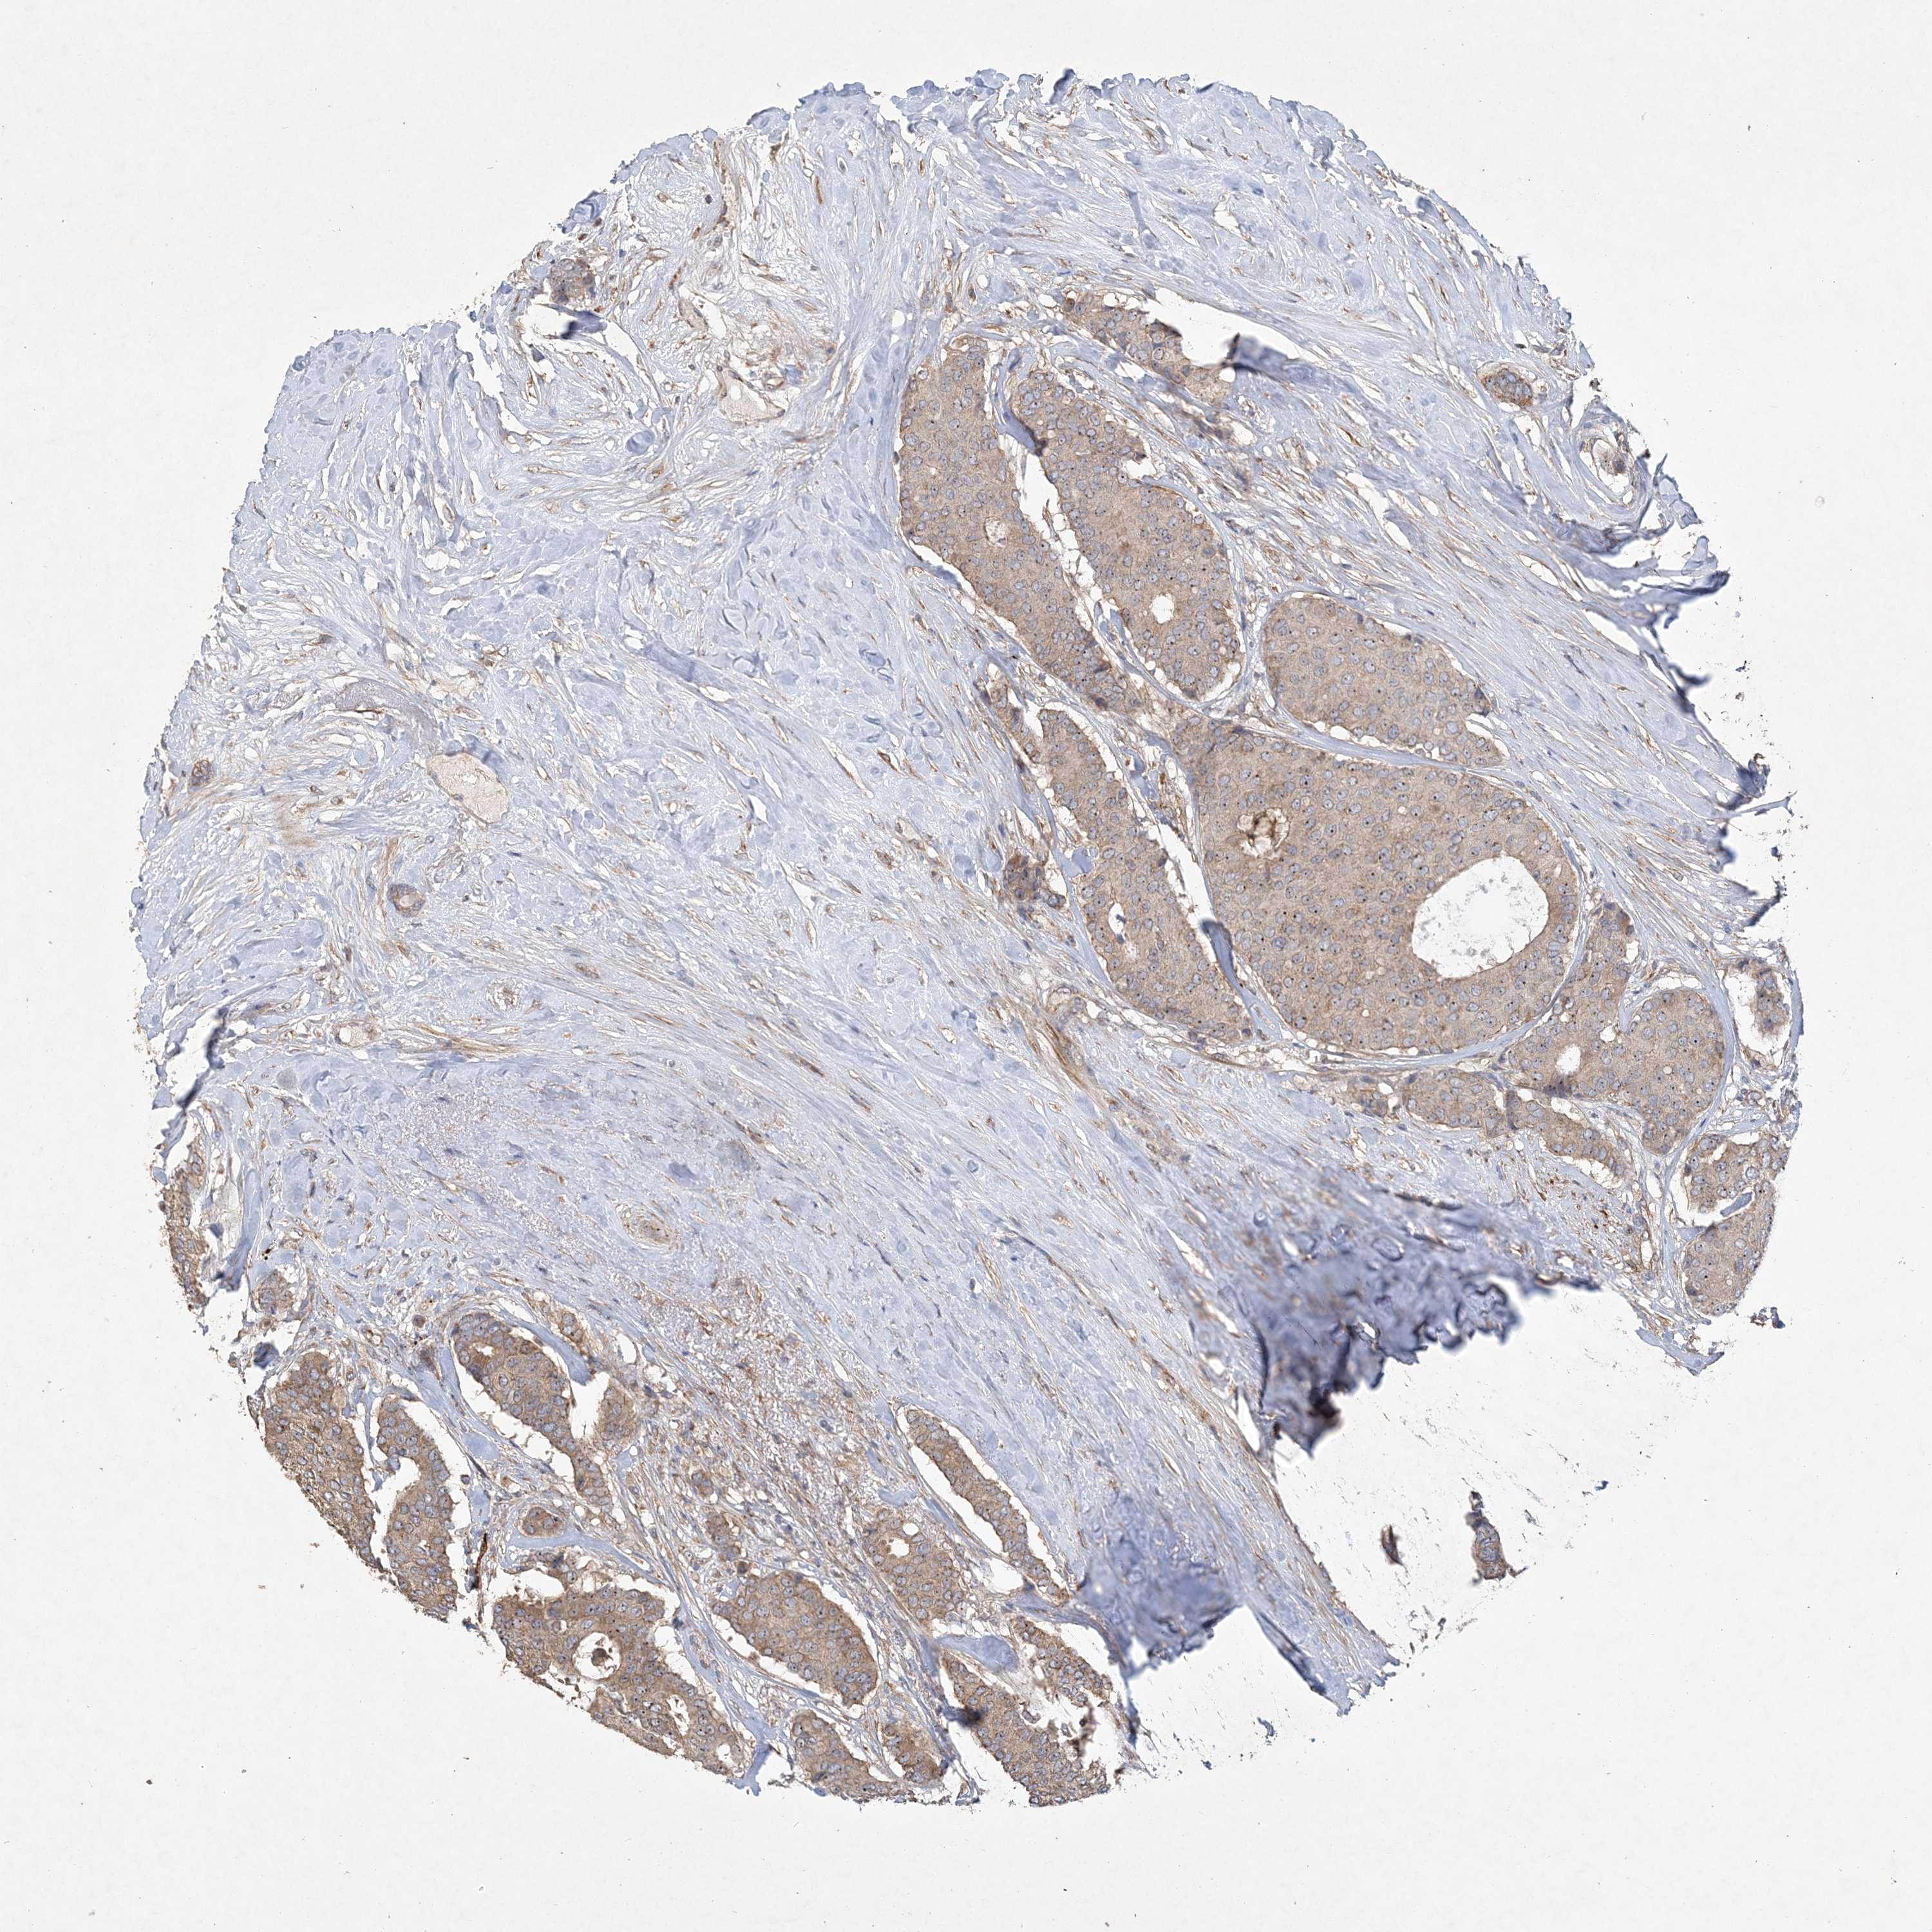

BRCA TCGA BRCA VALIDATION PROTEIN EXPRESSION

Breast cancer

Breast invasive carcinoma